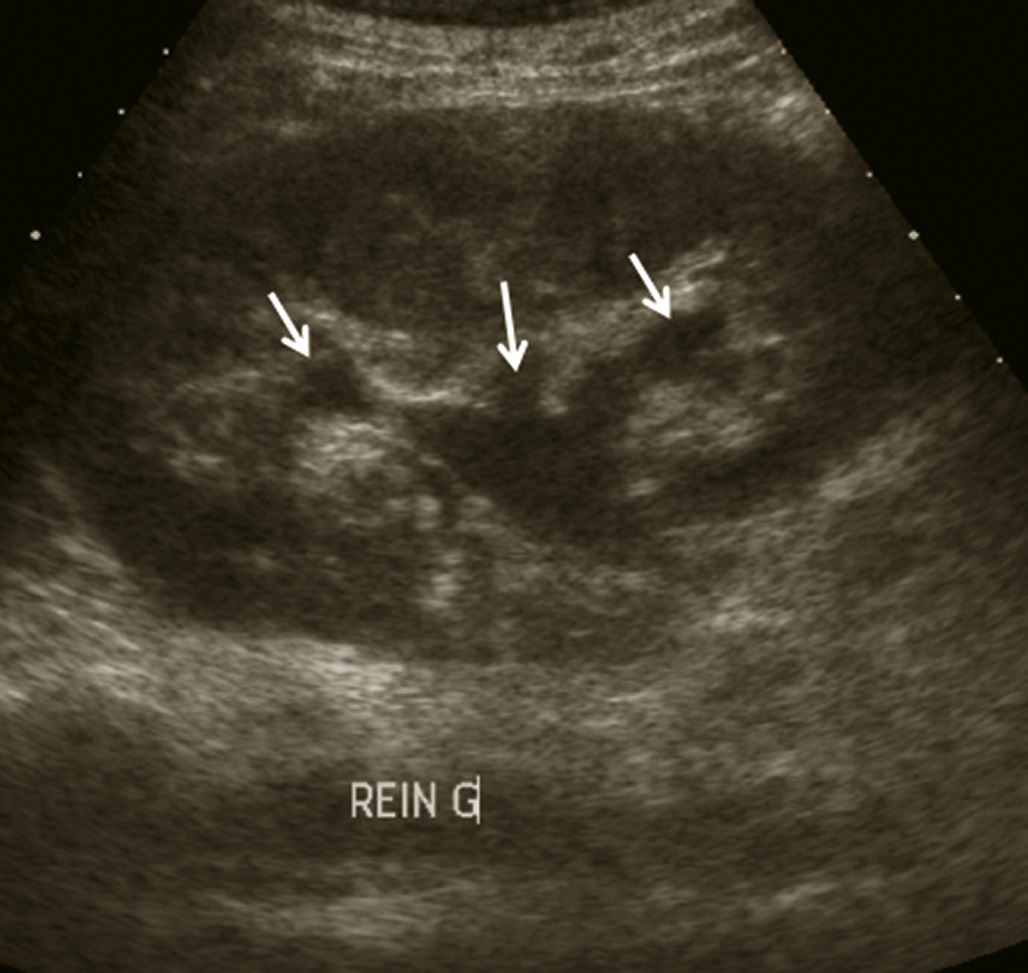

L’échographie abdominale a l’inconvénient d’être opérateur-­dépendante. Ses principales indications sont la lithiase biliaire et ses complications, des douleurs abdominales chez les patients minces et surtout chez la femme pour rechercher une pathologie gynécologique en utilisant le cas échéant des sondes endocavitaires. Ainsi, l’échographie est utile pour affirmer la lithiase biliaire et la cholécystite aiguë (fig. 1) ou objectiver une dilatation de la voie biliaire principale (VBP), rechercher une urétéro-hydronéphrose et des signes indirects en cas de colique néphrétique (fig. 2 et 3), débrouiller le diagnostic des douleurs abdomino-­pelviennes chez la femme.

Colique néphrétique

L’échographie peut montrer une discrète asymétrie des cavités excrétrices rénales, voire l’obstacle lithiasique avec dilatation d’amont (fig. 2 et 3). L’uroscanner complète le bilan et localise si besoin le calcul. Outre le traitement de la cause (calcul, compression extrinsèque…), le traitement antalgique est primordial : anti-inflammatoires non stéroïdiens (AINS), paracétamol, anti­spasmodiques voire dérivés morphiniques. On procédera à la pose d’une sonde urétérale en cas d’anurie (rein unique), de fièvre sur rétention du haut appareil ou de crise hyperalgique.